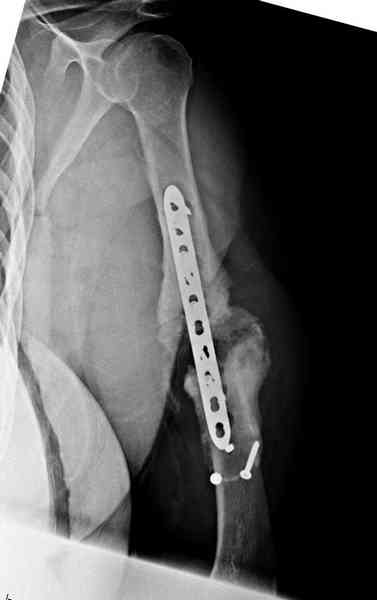

Как видно из выступлений коллег, способы фиксации

ложного сустава плеча могут быть различными, кто-то предпочитает аппаратом Илизарова (Соломин), пластинами (Волна) или интрамедуллярным гвоздем (Челноков).

Первичную пластину убрали недели 6 назад из переднего оригинального доступа, и из-за подозрительности тканей вокруг пластины, решили провести реконструкцию поэтапно.

Хотя сам не стороннник применения более массивных

имплантов для плеча, но для этого случая сделали

исключение. На снимке 4А диаметр мягких ткани около 20 см, при весе больной более 135 кг, и также выступление Андрея Волны подстегнуло к применению более массивной 4.5 мм локинг пластины.